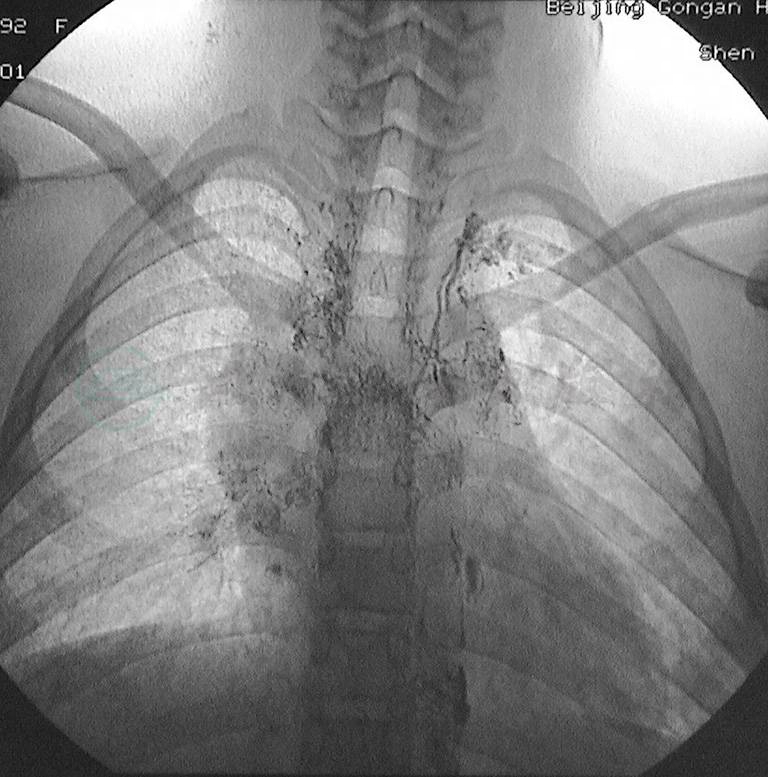

3.乳糜瘘也可发生在有淋巴管结构缺陷、乳糜反流所至的腹膜后各部淋巴管及其所属的脏器,乳糜漏出积聚在腹膜后(图3),最终造成乳糜性腹水、乳糜性胸腹水甚至单纯乳糜性胸水。

图3直接淋巴管造影显示髂淋巴管瘘